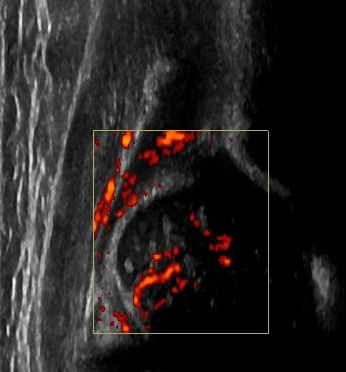

Typ D dach kostny bardzo niewystarczjący, brzeg kostny spłaszczony, dach chrzestny przesuniety dogłowowo ( szczyt głowy jest niżej w stosunku do szczytu dachu chrzęstnego) u noworodka z prawidłowym ukrwieniem głowy,widac wchodzace naczynia od strony krętarza(tędy płynie główne ukrwienie)

Typ IV 6 tyg dach kostny zły brzeg kostny płaski dach chrzęstny przesunięty doogonowo ( szczyt głowy jest wyżej w stosunku do szczytu dachu chrzęstnego)

Typ IV panewka II ale głowa całkowicie poza stawę nie zawsze paneka musi byc płaska aby głowa wysunęła sie z niej,wystarczy jak w tym przypadku nadmierna wiotkość tkanek miękkich( torebki ,więzadła głowy i więzadeł pozastawowych) wystepujaca najcześciej albo z powodu rodzinych albo najprawdopodobniej uszkodzenia móżdżku i zwiazanego z nim układ sterującego napęciem stawu.